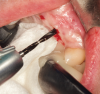

In preparation for the surgical procedure, modest bone grafting and soft-tissue augmentation was used to create more ideal oral parameters to receive the implants. Five implants (NobelActive®, Nobel Biocare, nobelbiocare.com) were placed in the maxillary anterior esthetic zone using haptic robotic guidance (Figure 3 and Figure 4). The procedure was entirely flapless, contributing to minimizing trauma for the patient. The surgeon, in full control of the robot, guided the arm to the planned implant positions while inspecting the soft-tissue type at the emergence, noting the bone quality, and monitoring adherence to the plan with the robotic system's intraoperative accuracy verification. The real-time audio and visual updates confirmed that the clinical parameters had been successfully achieved.

Fig 3. Implant placement using haptic robotic guidance. As osteotomies are prepared, the robotic arm locks the handpiece at the correct spatial position both in bodily direction and angulation, and as the clinician drills to proper depth, the arm prohibits further drilling apically.

Figure 3

Fig 4. Implant placement using haptic robotic guidance. As osteotomies are prepared, the robotic arm locks the handpiece at the correct spatial position both in bodily direction and angulation, and as the clinician drills to proper depth, the arm prohibits further drilling apically.

Figure 4